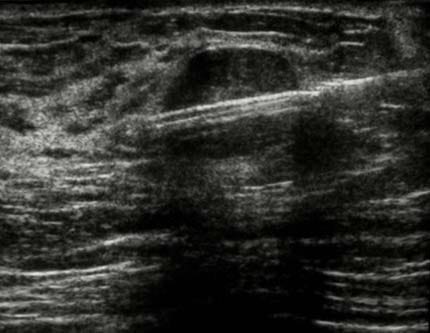

Sous Guidage d'Imagerie (Échographie ou Tomosynthèse) : Prélèvement de fragments de tissu mammaire pour l'analyse histologique, permettant de caractériser une lésion suspecte du sein.

Le geste est effectué sous contrôle visuel continu (Écho ou Scanner) pour une précision maximale.